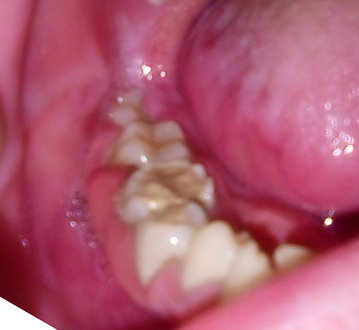

В течение трех дней опухает нижняя десна со стороны щеки. Шишки нет, отек прото. Не могу сказать что болит, но ноет. При надавливании на зубы боли нет, но при постукивании — в двух боль чувствуется. Один зуб без нерва, лечила год назад. Другой с нервом, лечила месяц назад.

Что это может быть? И как мне еще 2 дня протянуть, нет возможности пойти к специалисту.

Плохо, что два дня еще нельзя пойти к специалисту. Пополощите раствором соды и соли, по пол чайной ложки на стакан воды. Припухает очевидно из-за проблем в корнях какого-то из двух зубов, причем я склоняюсь, что вероятнее в том, который лечился месяц назад. Возможно, после установки пломбы возник асептический некроз пульпы и его последствия, срок в месяц — как раз подходят под данную картину. Хорошо было бы приложить рентген-снимок.